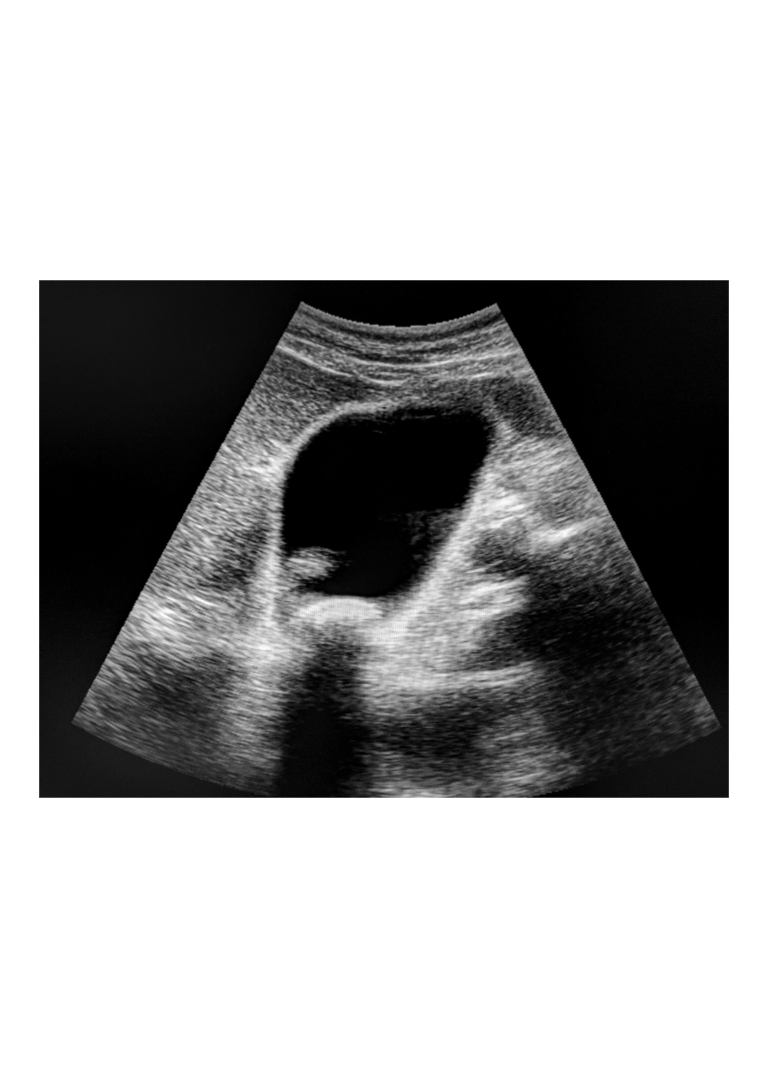

Ecografia addominale: è il metodo diagnostico di prima scelta per visualizzare i calcoli all'interno della colecisti. È non invasiva, veloce ed efficace.